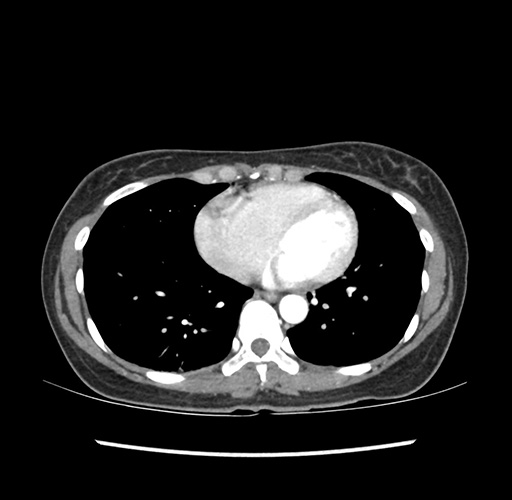

Imaging Analysis

Look through the patient's CT scan to identify any areas of concern for the necessary procedure.

Based on your CT findings, which issue(s) would give reason for "planned slowing down moment(s)" in this case?